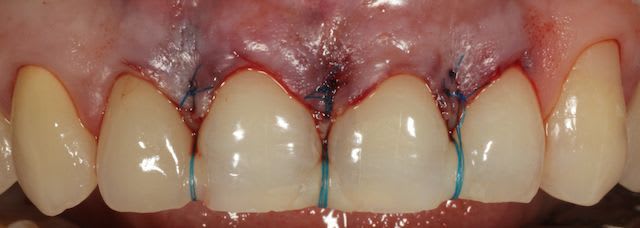

Puisqu'on parle un peu de muco, je vous propose un cas de lambeau positionné coronairement modifié selon la technique dite de Zucchelli.

En fait le principe c'est de reporter la hauteur de tes recessions au niveau des papilles et de faire tes incision en fonctions, effectivememnt le lambeau est dissequé au delà de LMG pour pouvoir suturer sans tension, les papilles saignent parce qu'elles sont été désepithelialisés.

Pour le fil, il existe du transparent mais franchement c'est pas vraiment un problème pour le patient si tu le temps de lui expliquer.

à 6 semaines.